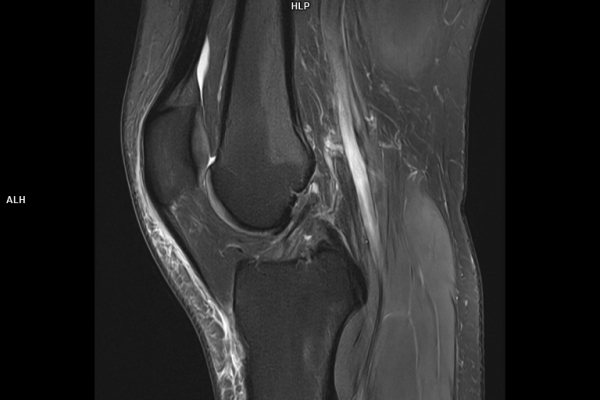

Detailbild MRT

Die MRT (Magnetresonanztomographie) arbeitet mit Magnetfeldern und Radiowellen und eignet sich besonders für Untersuchungen der Weichteile wie Gehirn, Muskeln oder Gelenke. Die CT (Computertomographie) nutzt Röntgenstrahlen und liefert schnelle, hochauflösende Bilder, insbesondere für Knochen, Lunge oder innere Organe. Die Wahl der jeweiligen Untersuchung richtet sich an das individuelle Krankheitsbild und wird bei der Überweisung festgelegt.